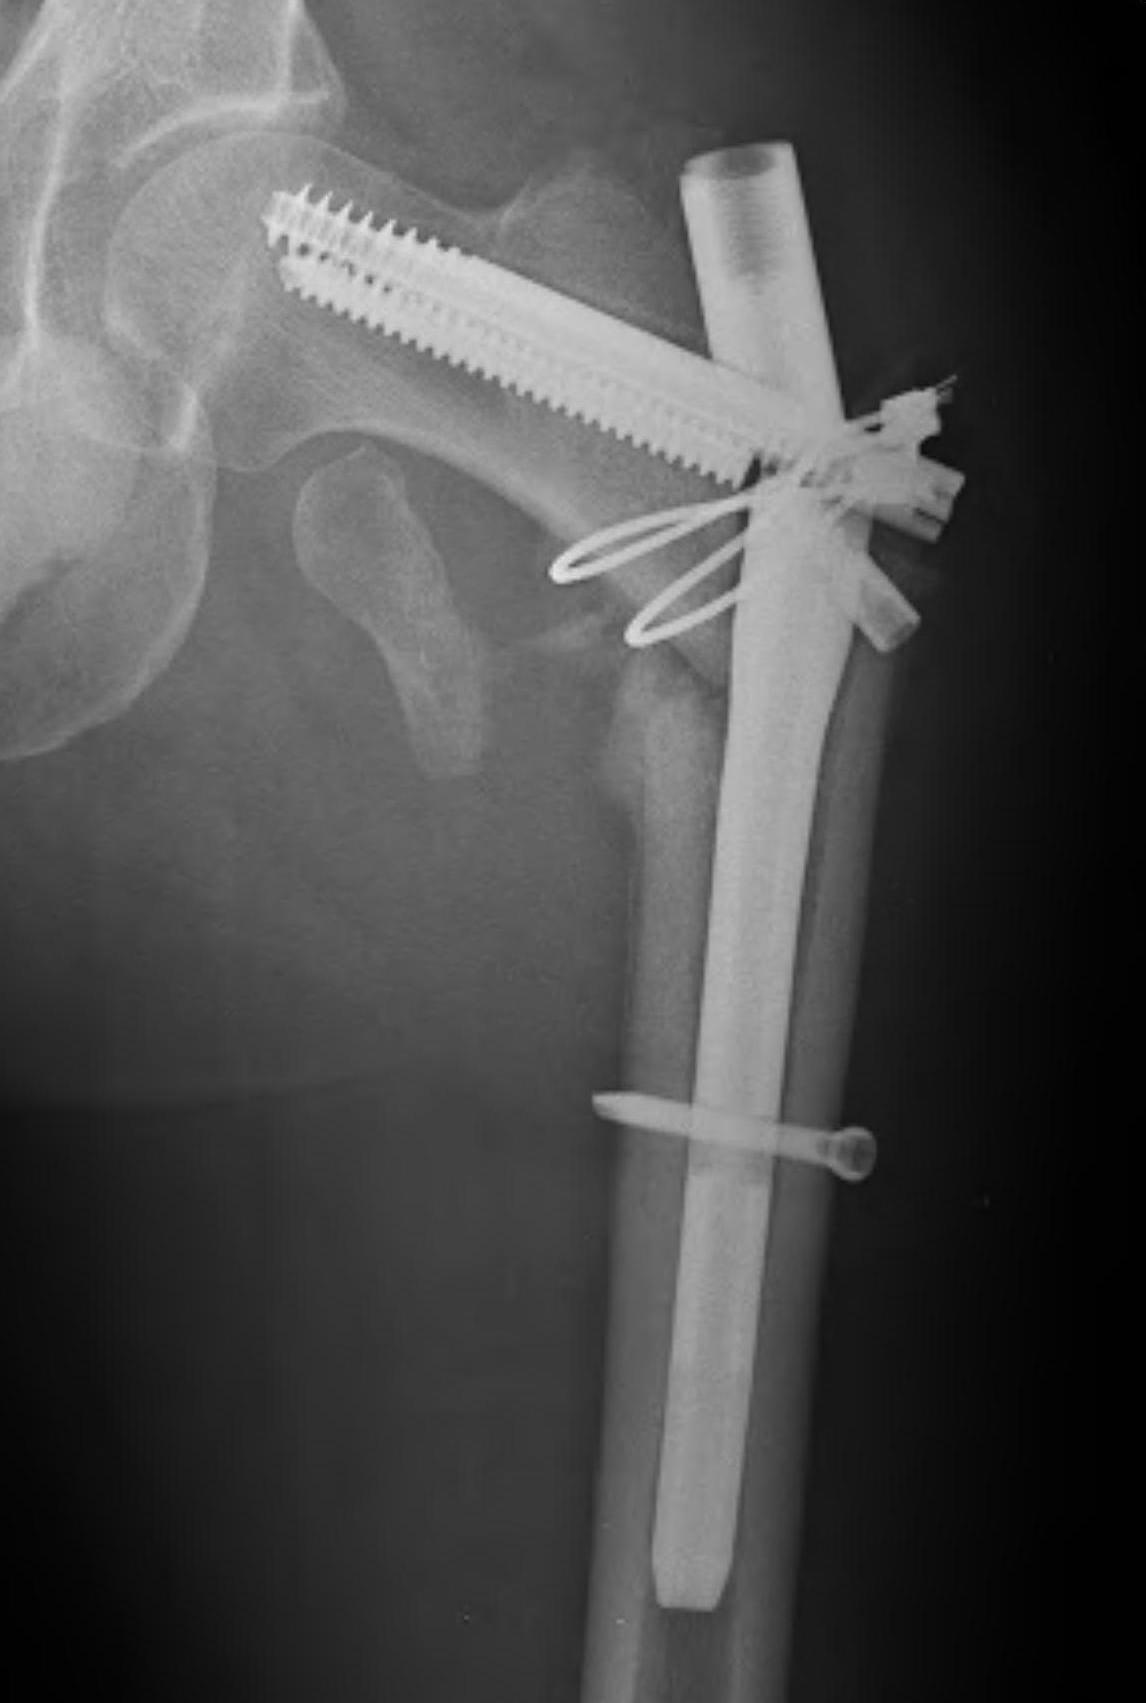

2. Longer spiral fractures

- clamping and cerclage wiring with longer spiral fractures